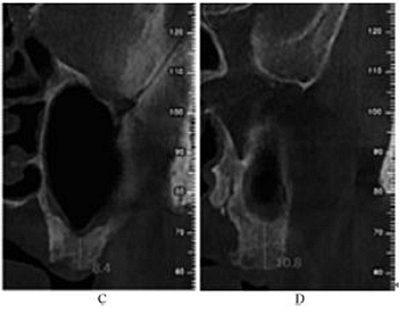

CBCT示:左側鼻甲水腫,左側上頜竇內可見黏膜呈半圓形隆起,密度均勻升高,未見鈣化及明顯骨質破壞;26牙剩余牙槽突高度(residual bone height,RBH)1.8mm,27牙RBH4.2mm,28牙RBH11mm,上頜竇頰側骨壁厚度約1mm(圖1)。

圖1 術前CBCT

注:A,矢狀面;B,26頰舌向切面;C,27頰舌向切面;D,28頰舌向切面。